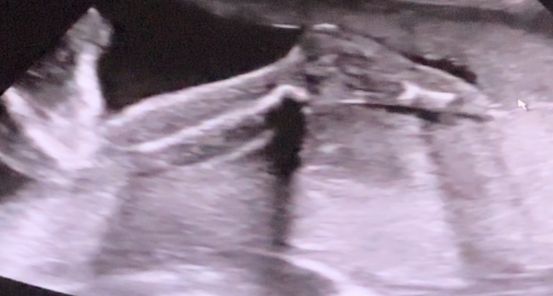

23/4 Нед узи

638 гр ЧСС 136, шустрый парень